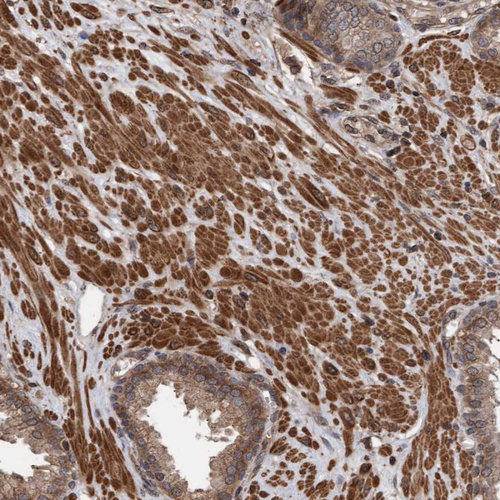

Immunohistochemical staining of human cerebral cortex shows strong cytoplasmic positivity in neurons.